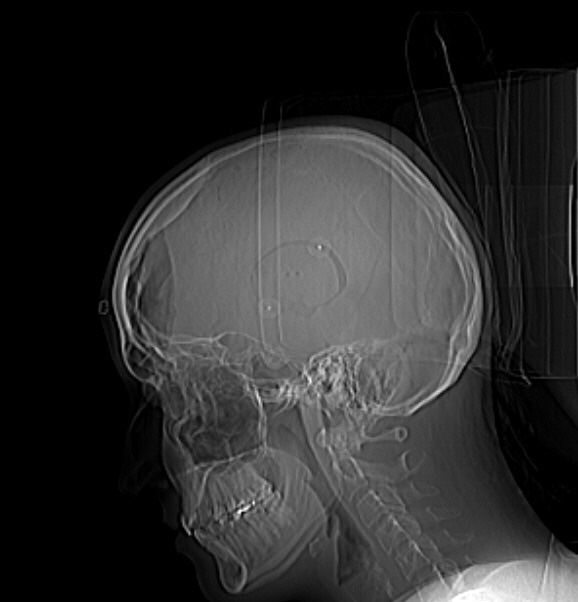

Darunter verbirgt sich das nächste „Dokument“ von der Operation. Dies ist allerdings nur via Röntgen, bzw. MRT sichtbar.

Eine Schädelausfräsung, die nach der Operation wieder einigermaßen passend mit zwei Nägeln festgespackst wurde. Durch dieses Loch wurde genau heute vor zwölf Jahren zum ersten Mal mein Untermieter live und in Farbe durch die Neurochirurgen gesehen. Schade, dass sie mir damals kein Foto davon gemacht haben. Ich glaube wenn irgendwann mein Schädel nochmal geöffnet wird dann bitte ich darum. Ich würde das Teil gerne mal wirklich auch real sehen können.